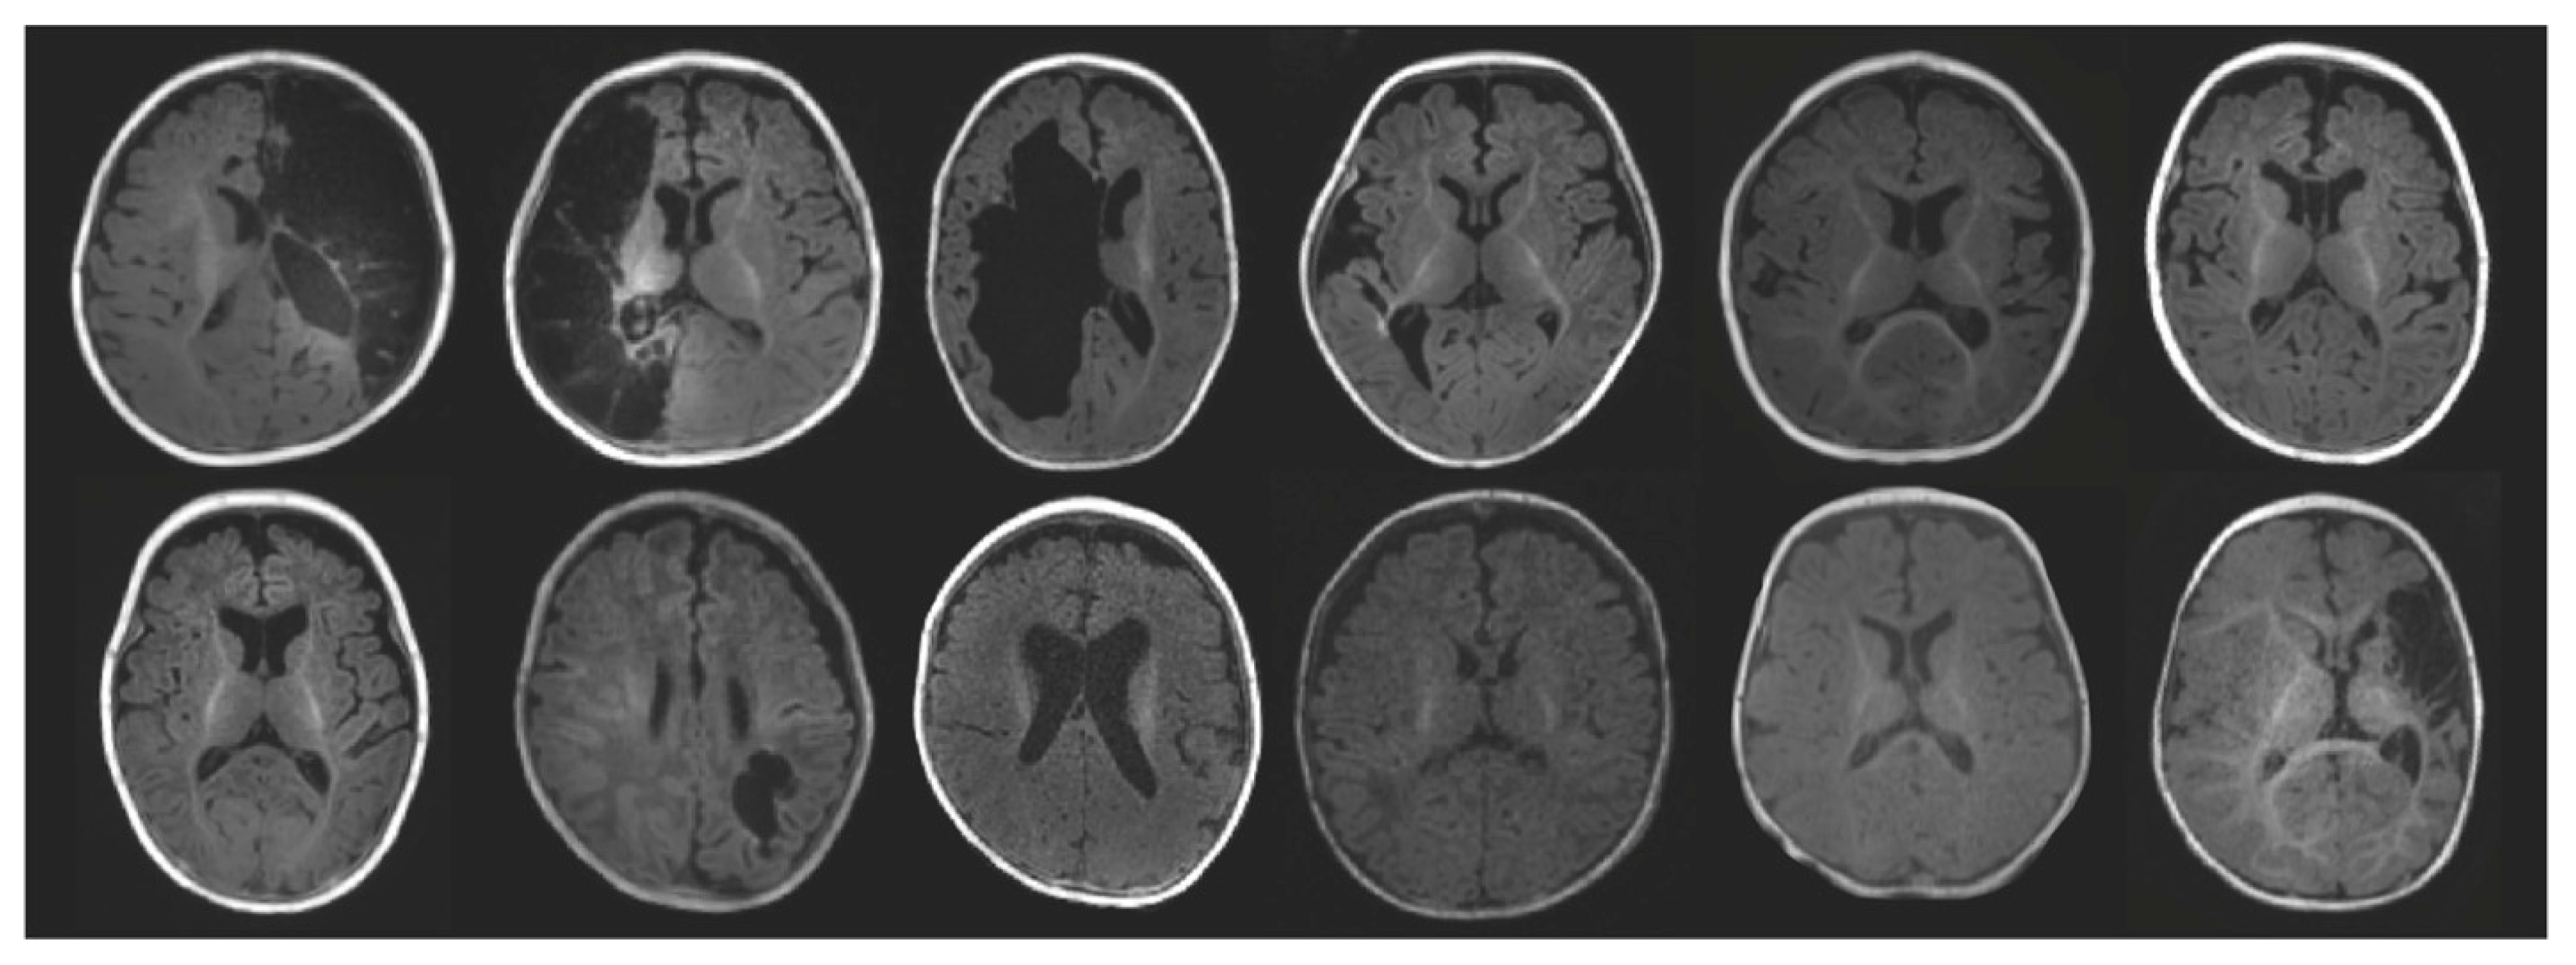

2.1. Participants

| Infants with Perinatal Brain Injury (N = 12) | |

|---|---|

| Sex | 3F, 9M |

| Primary Diagnosis | |

| Ischemic or hemorrhagic perinatal stroke | 6 |

| Intraventricular hemorrhage | 2 |

| PVL | 1 |

| HIE | 3 |

| Lesioned Hemisphere | |

| Left | 4 |

| Right | 4 |

| Bilateral | 4 |